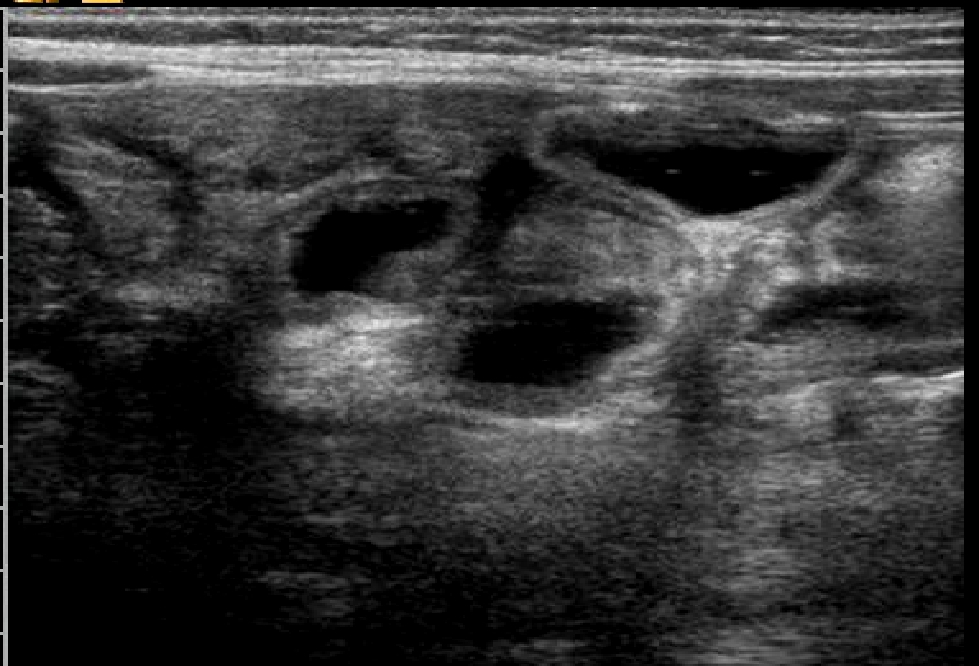

La biopsia duodenale mostra una mucosa di tipo

3B con villi corti a base ampia e rarefatti come da patologia

malassorbitiva; presenti i microvilli; evidenza di fitto

infiltrato linfoplasmacellulare e localmente eosinofilo del

corion con ectasie linfatiche polifocali (fig.

3)